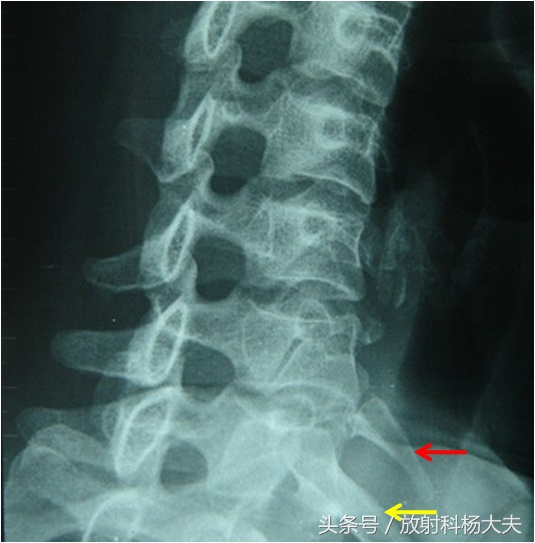

红箭为多出的肋骨,为颈肋。黄箭为正常肋骨

颈肋是指第7颈椎一侧或两侧长出肋骨,为先天性畸形。一般颈肋无症状,仅有少部分的颈肋患者可产生臂丛神经和锁骨下血管受压而出现一系列症状和体征,即“颈肋综合征”。颈肋综合征的一个主要临床表现是锁骨上窝出现质硬包块,就像上面的老王那样。主要表现为臂丛神经下干支配去的感觉和运动障碍,几乎全部单侧发病。

有学者将颈肋从形态上分为横突过长、不完整颈肋、完整颈肋、特殊形态4种。不完整颈肋和完整颈肋的患者锁骨上窝的质硬包块是其主要临床表现,也是导致患者来看病的主要原因之一。完整颈肋者看都能看出来,不完整颈肋则需要用手,就像杨大夫那么用手触摸后发现。而在横突过长者者无明显肿块,则不易发现,须结合临床体检。